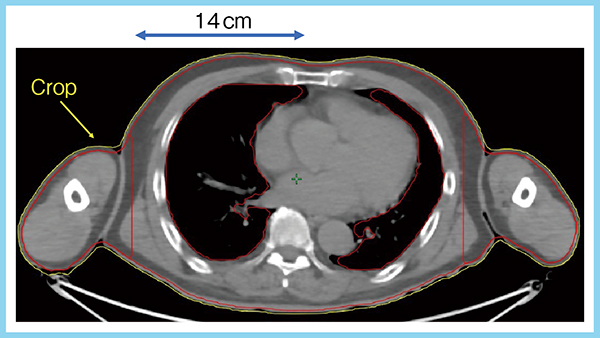

治療計画に当たり,頭頂部から足先まで撮像された身長162cmの男性症例のPET/CTのデータセットを使用した。本研究で最も重要なポイントは,planning target volume(PTV)の設定である。図1の黄色のライン(ー)は体輪郭,そこから3mm内側をPTVとし(ー),体の中心から左右に14cmの部分をPTV-BODY,その外側をPTV-ARMと設定して(図1),D98%,D95%,D50%,D2%を評価した。体幹部と腕を分けたことで,腕にも十分な線量が投与されるよう最適化を図った。

図1 PTVの設定(参考文献1)より引用転載)